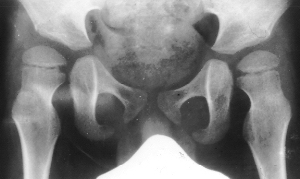

post-operatively. At 6 y.+ 2m. (post-op. 2y.), flex; 140 degrees, abd;

35 degrees,p-angle; 35 degrees bilaterally,Thomas; 10 degrees on the right

and 15 degrees on the left;. The x-ray showed dramatical improvement of

the subluxation and acetabular coverage.